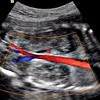

УЗДС НПВ и ее ветвей

УЗДС НИП и его филиалы. Метод неинвазивного обследования нижней полой вены и ее основных ветвей с помощью ультразвуковых волн и специальных датчиков. Исследование позволяет оценить диаметр венозного ствола, свет вен и состояние клапана, а также представление о существующем венозном тромбе, важном не только для диагностических целей, но и для определения тактики и срочности хирургического лечения. Методика применяется при диагностике воспалительных процессов в стенках вен и клапанов, для выявления сгустков крови и определения их точного местоположения. Ультрасонография и ее ветви необходимы пациентам с кава-фильтром, установленным для оценки их состояния. Процедура проводится в амбулаторных условиях, необходимо соблюдать диету в течение нескольких дней до УЗИ, поскольку исследуемая область расположена на кишечном уровне.